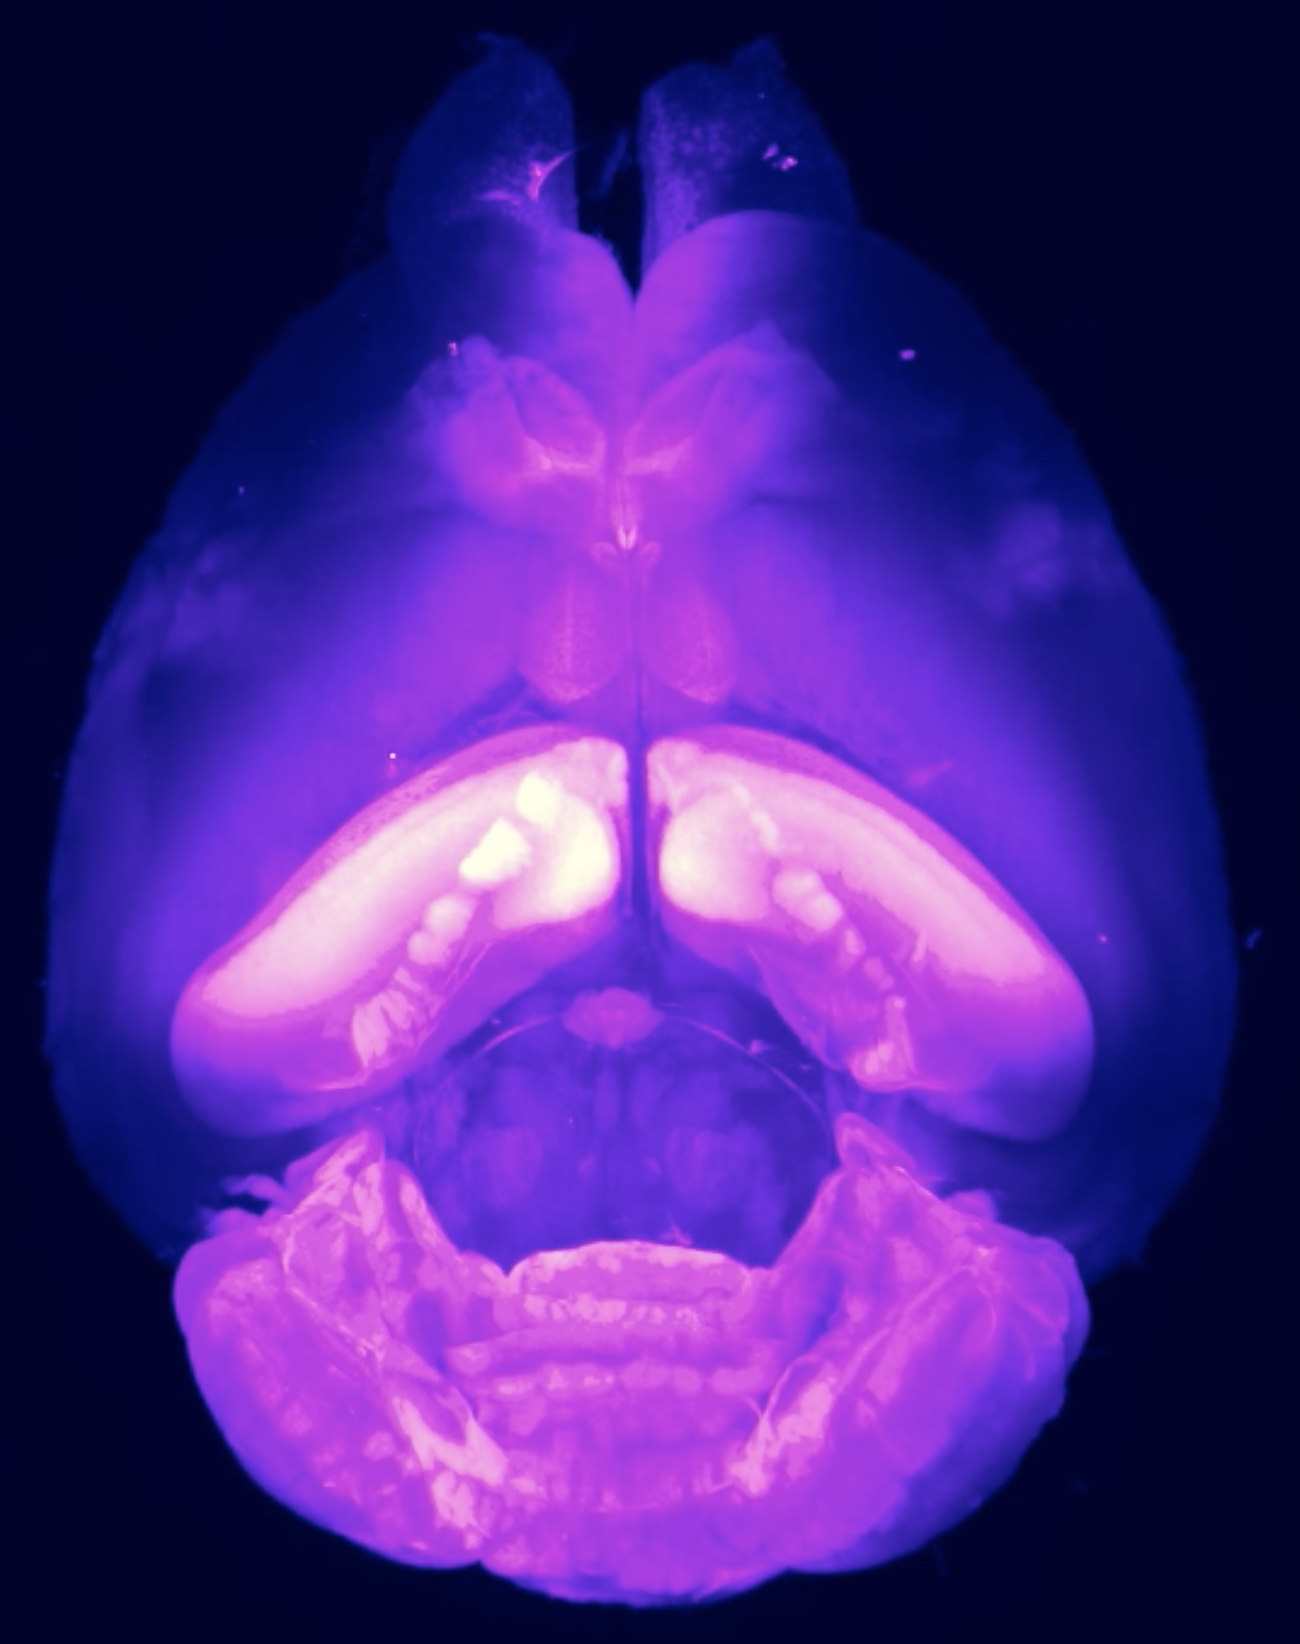

私たち生命は、化学分子の集合体でできています。生体に存在する分子の濃度・局在・相互作用・反応により、生命は成り立っています。しかし、個々の分子がどのように機能しているのか、その全容は未だ解明されていません。私たちのグループでは、「化学」の力で優れた機能を持つ「分子プローブ(生体探索/制御分子)」を創り出し、生命現象を分子レベルで理解・制御することを目指しています。分子を創る「有機化学」、化学で生命に迫る「化学生物学」、生命を知る「分析化学」の融合により優れた分子プローブを開発し、ヒトやマウスといった個体レベル(In vivo)での機能解析・制御法の開発に挑戦しています。

具体的には、生体内で重要な機能を発揮している特定タンパク質の機能解析、精神疾患・神経疾患などに関与が示唆される脳内の特定細胞の解析/機能化、がんの診断・治療につながる分子技術の開発などを多角的に取り組んでいます。これらの取り組みを通じ、未知の生体メカニズムの解明、そして分子情報を基軸とした革新的な医療診断・応用の実現を目指しています。